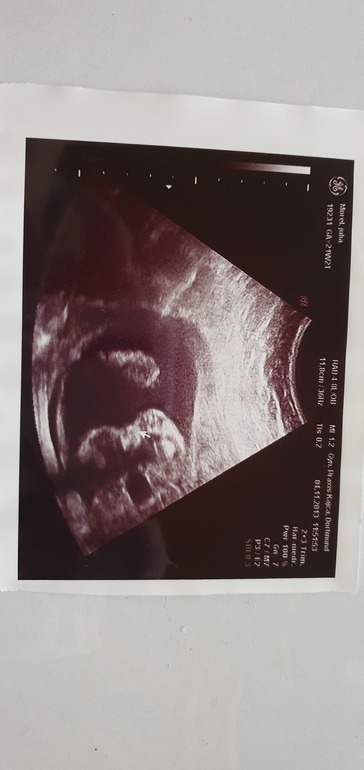

Вот в 19 недель

Алиса на 16 неделе.